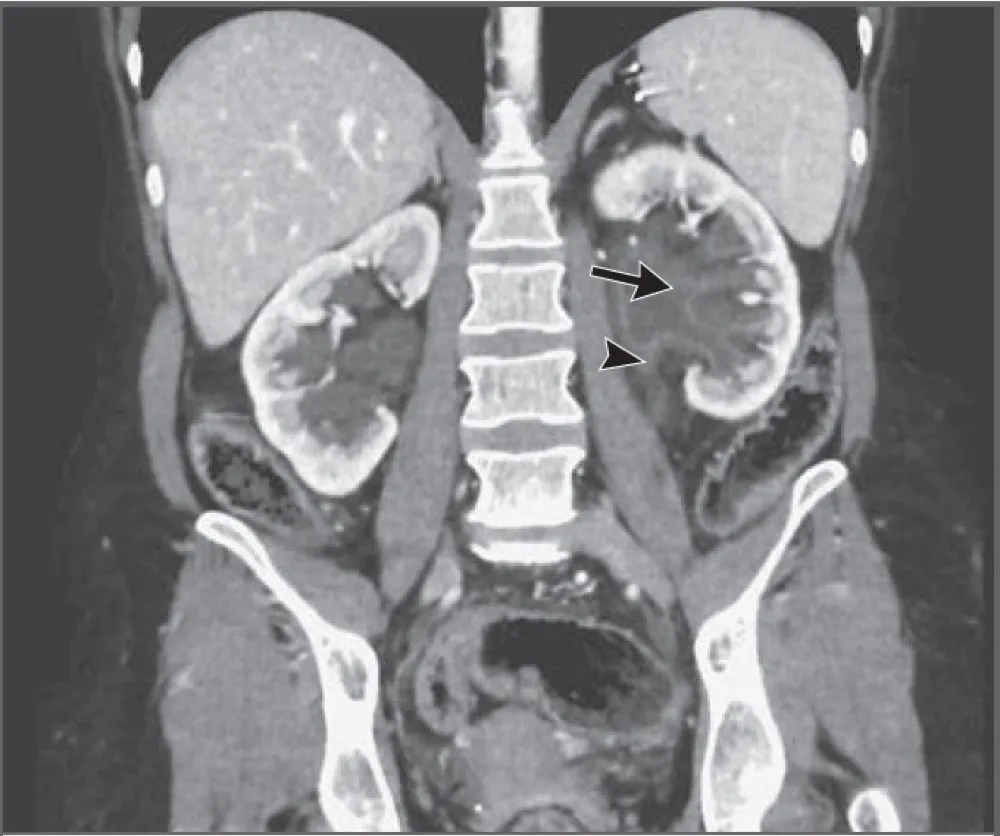

Desta forma, uma Uro-TC foi realizada a fim de determinar se a nefrolitíase poderia justificar o quadro de

ITU recorrente. A urografia por TC revelou espessamento urotelial e leve dilatação do sistema coletor e ureter esquerdo, com detritos sem realce ao contraste, e que envolviam os cálices renais esquerdos (Figura 1).